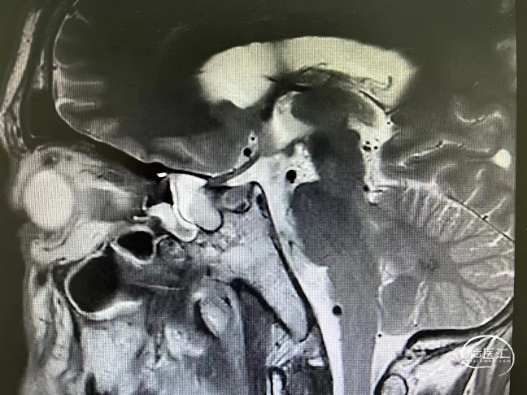

术前MRI平扫T2冠、矢状位:右侧蝶窦高信号占位,右侧视神经受压。

术前MRI增强扫描冠状位:右侧蝶窦占位,无明显强化。